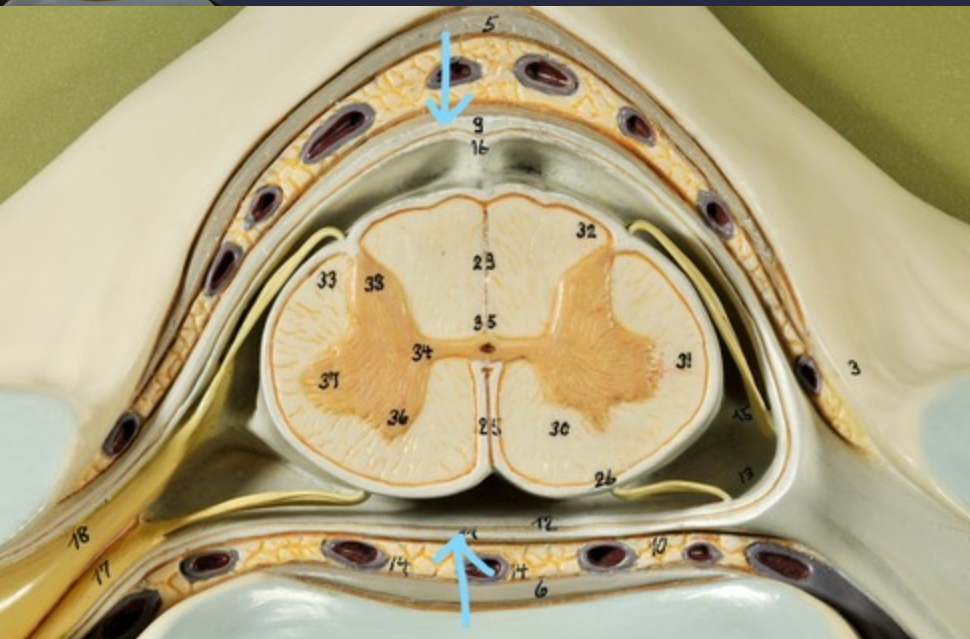

Dura mater (outermost layer)

White matter of spinal cord

Gray matter of spinal cord

Ventral horns (of gray matter)

Lateral horns

Dorsal horns

Anterior columns of white matter

Lateral columns of white matter

Posterior columns of white matter

central canal of spinal cord

Pia matter

Subarachnoid space

Arachnoid matter

Subdural space (brown line)

Dura matter

Epidural space

Dorsal root ganglion

Dorsal root

Ventral root